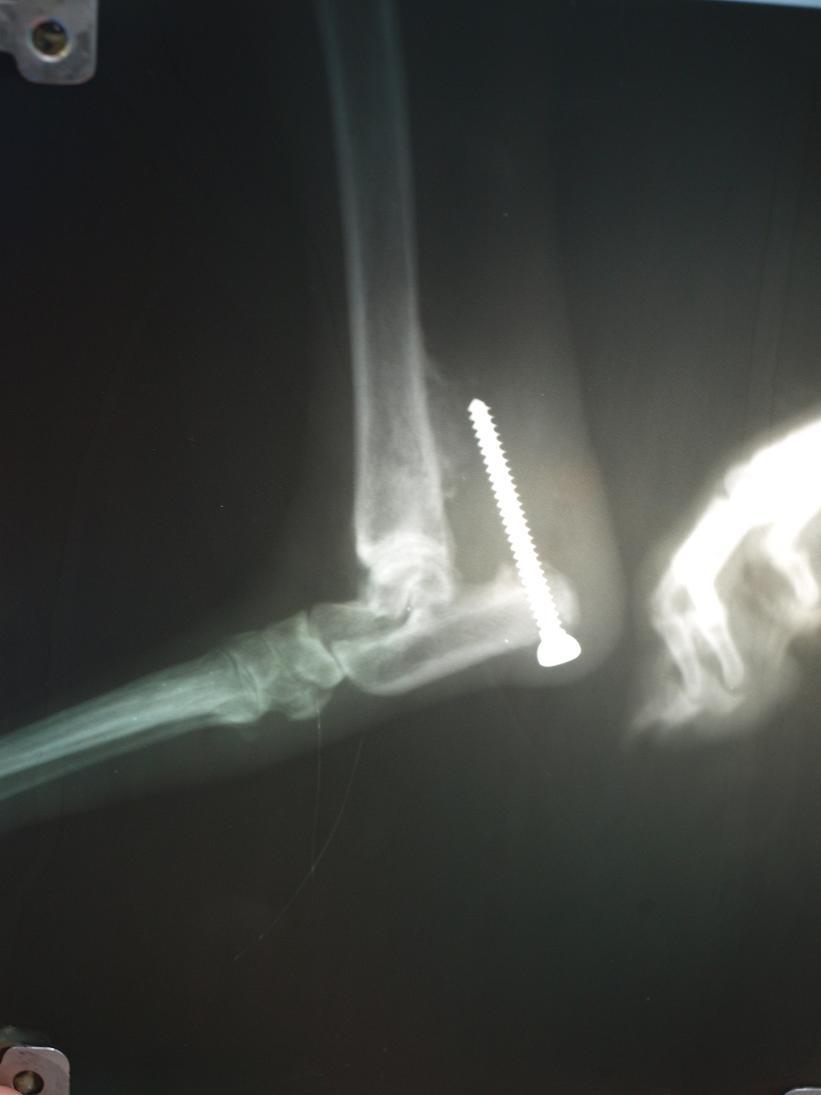

Эту лайку травмировал на охоте кабан. Собаке была оказана первая хирургическая помощь, в том числе сшивание поврежденного ахиллового сухожилия. Через неделю после травмы выяснилось, что концы сухожилия не сомкнуты и собака опирается на всю стопу.

Через два месяца после травмы хозяин собаки обратился в нашу клинику. К этому времени расстояние между концами сухожилия составляло 4 см, поэтому натянуть и сшить сухожилие не представлялось возможным.

Для замещения дефекта мы использовали лоскут широкой фасции бедра этого же животного сложенный вчетверо. Иммобилизация конечности производилась стягивающим винтом, проведенным через пяточную и большеберцовую кость.

К концу шестой недели лечения стягивающий винт вырвался из берцовой кости, но к этому времени сухожилие срослось.